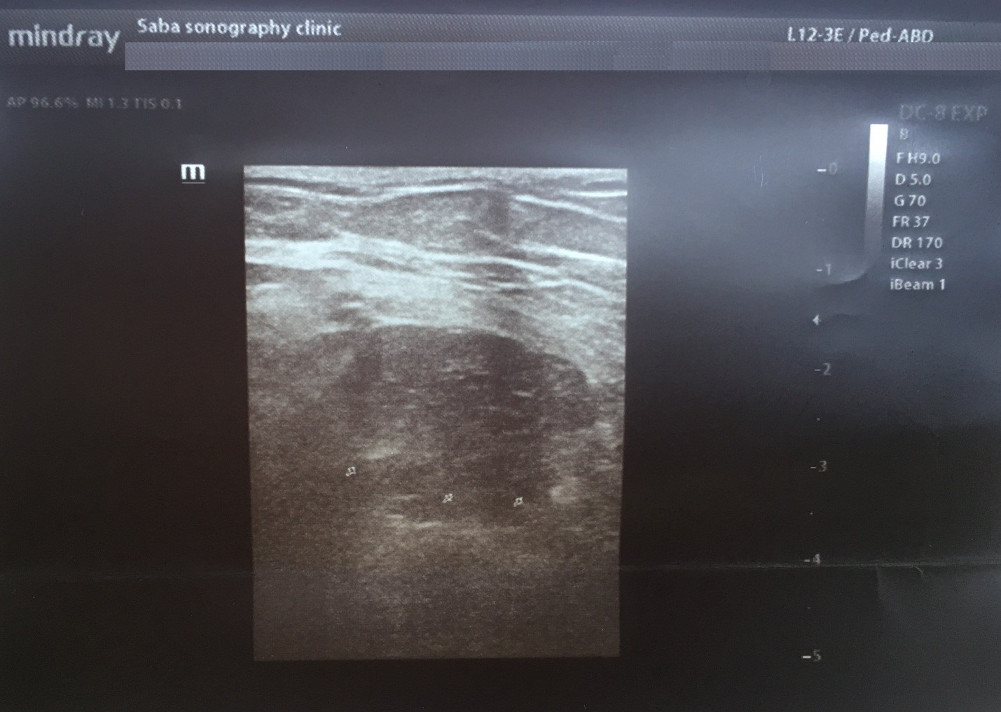

Ultrasound findings demonstrated a hypoechoic encapsulated multi-cystic lesion (M: 9*8*6.5 cm) inside the anterior quadriceps femoris muscle. There was a smooth calcification in the cyst wall. The most important differential diagnosis based on imaging findings was hydatid cyst (Figure 1 [Fig. 1]).

Figure 1: Ultrasound of the thigh revealed an encapsulated multi-cystic lesion with an indistinct margin (arrowheads) or a well-defined hyperechoic wall (arrow) corresponding to a calcified, non-vital hydatid cyst